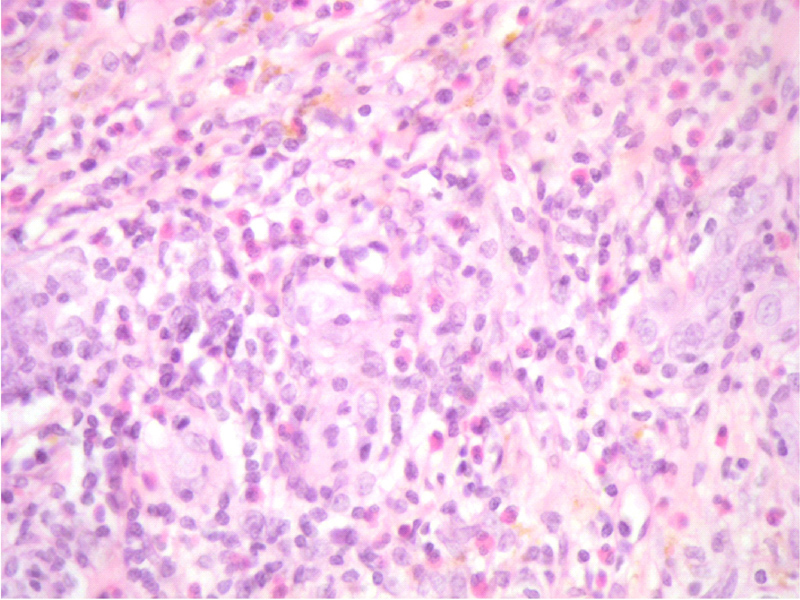

En la biopsia se observan cambios compatibles con la enfermedad de Kimura; Áreas con infiltrado eosinofílico, vasos prominentes y con hialinización de la pared. El estudio inmunohistoquímico positivo para CD34 (

Figura 4 y

Figura 5).

Figura 4. Áreas con vasos prominentes y con hialinización de la pared.

Figura 5. Prominente infiltrado eosinofílico con múltiples vasos con endotelio prominente (endotelio vascular puesto de manifiesto mediante inmunohistoquímica por expresión de CD34).